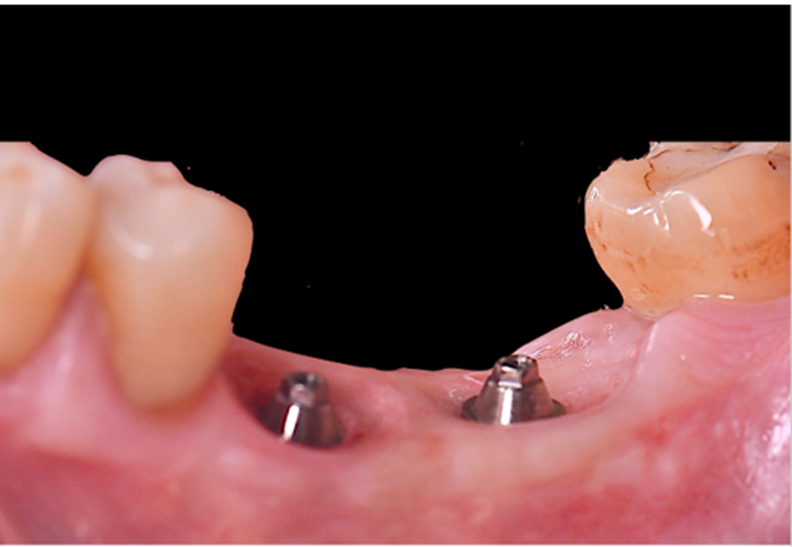

Selecionamos um caso clínico para ilustrar o fluxo de trabalho digital para Mini Cônico, onde foram planejadas duas coroas unidas nos elementos dentários 36 e 37 em zircônia monolítica, feitas sobre o pilar para próteses múltiplas.

Após o período de osseointegração dos implantes, a altura correta do transmucoso de cada Mini Cônico foi selecionada utilizando-se o medidor tunel check, e os pilares foram instalados com um torque de 20 Ncm. Sobre os componentes, foram confeccionados provisórios para a personalização do perfil de emergência.

Na etapa de escaneamento foi selecionado o transferente digital do Mini Cônico e optamos por trabalhar no fluxo e biblioteca do software Exocad (onde é realizado o design da prótese), o qual tem toda a linha de componentes da Implacil De Bortoli e de seus análogos digitais.

Neste caso, a prótese múltipla foi desenhada sobre o Mini Cônico e as duas coroas foram fresadas unidas. Após a maquiagem final da zircônia monolítica, as coroas foram parafusadas sobre o Mini Cônico com um torque de 10 Ncm.

Podemos acompanhar o passo a passo das etapas, desde a seleção da altura do transmucoso do Mini Cônico até a instalação das coroas unidas no fluxo totalmente digital sem a utilização de componentes metálicos.